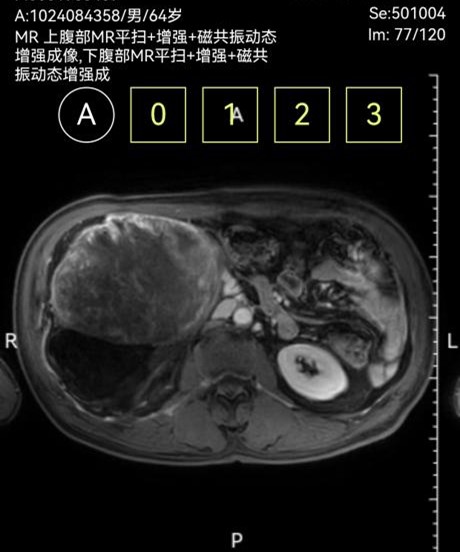

此次两名患者均因“腹部胀痛、包块及进食受限”入院,经增强CT三维重建及磁共振等检查,确诊为腹膜后巨大肿瘤。一例左侧腹膜后肿瘤,长径达30cm,重约4.8kg,紧贴腹主动脉及腹腔干,侵犯脾动脉根部及胰体尾、脾门、右肾及右肾上腺,与结肠系膜粘连紧密,挤压胃肠道引发不全梗阻;另一例右侧腹膜后肿瘤,长径40cm,重约3.2kg,侵犯结肠系膜根部血管,血供丰富,同时挤压肝门及十二指肠,存在右肾蒂损伤风险。